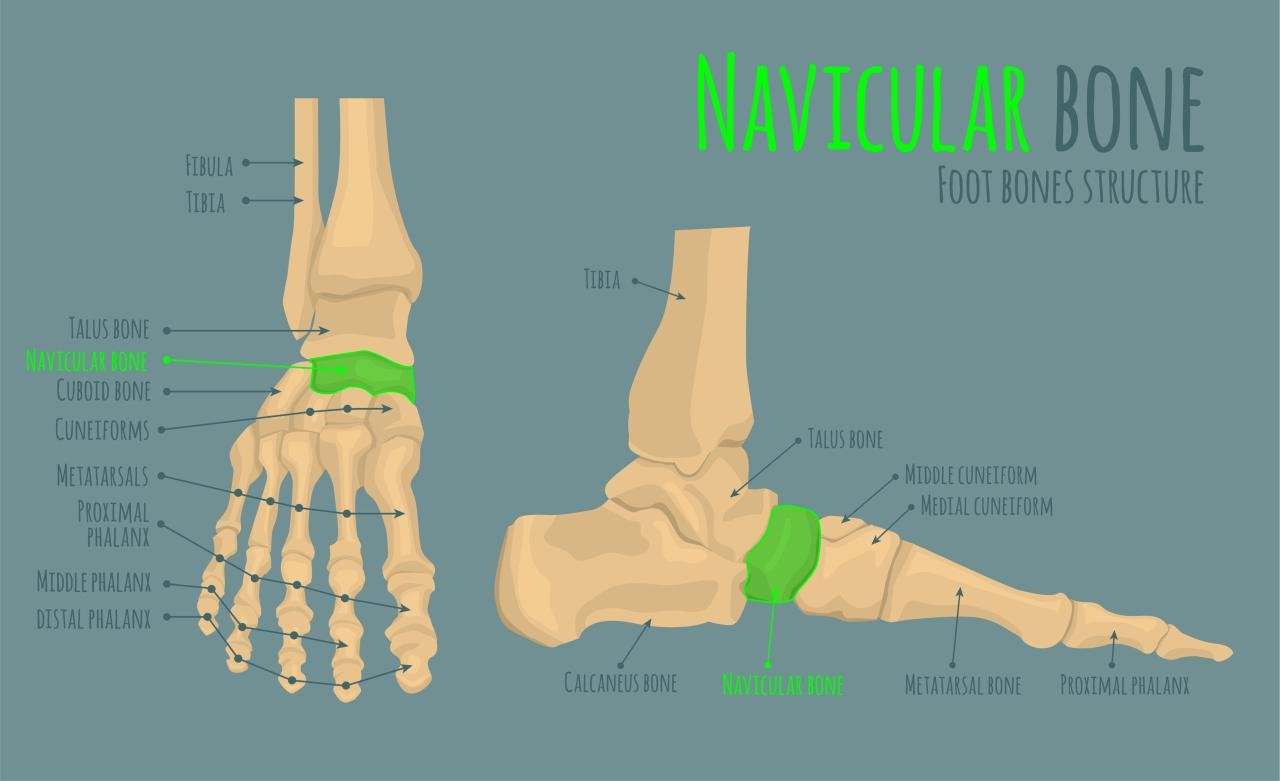

Accessory navicular surgery procedure is a groundbreaking solution for individuals suffering from accessory navicular syndrome, a condition that can cause severe foot pain and discomfort. This innovative surgical option not only alleviates pain but also restores mobility, enabling patients to return to their active lifestyles with confidence.

With advancements in medical techniques and technology, the accessory navicular surgery procedure has become a sought-after treatment. This procedure not only removes the accessory bone but also addresses the underlying issues that contribute to foot pain, ensuring long-lasting relief and improved quality of life.

What is accessory navicular surgery procedure?

The accessory navicular surgery procedure involves the removal of an extra bone in the foot to relieve pain and improve function.